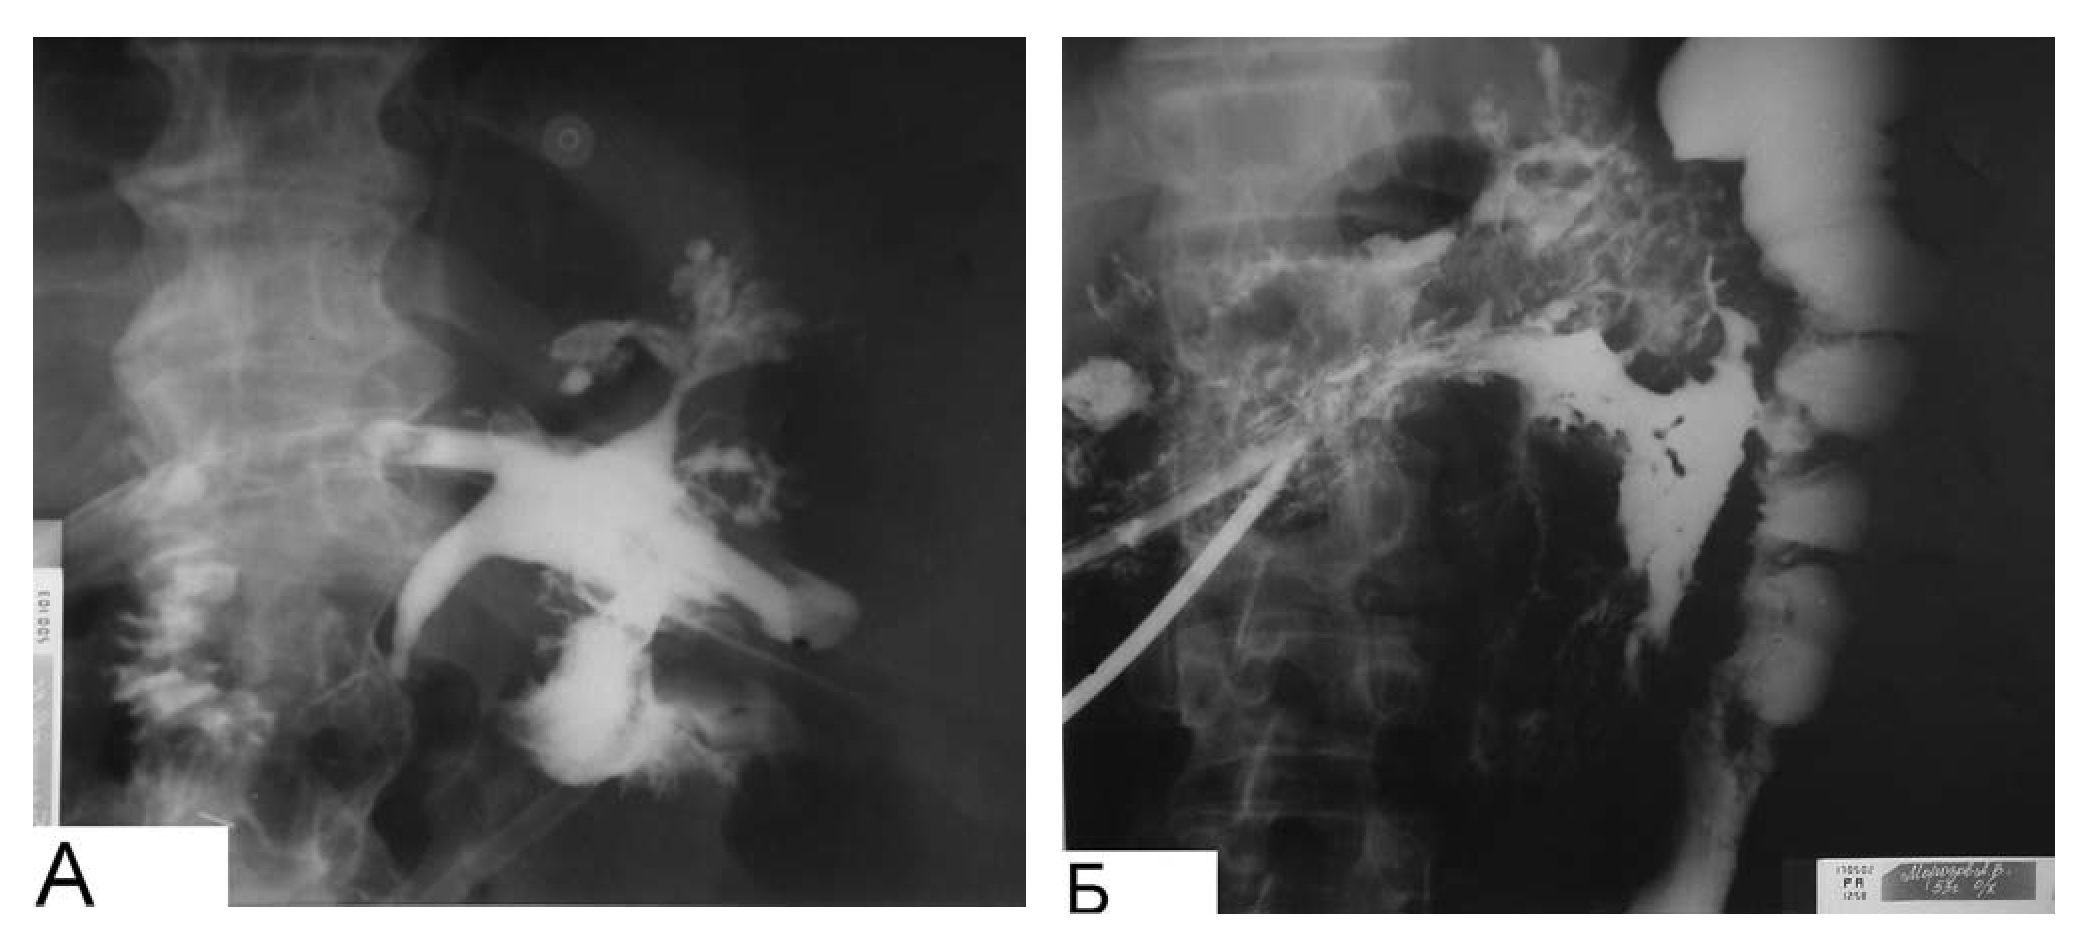

Рис. 3. Стандартные схемы дренирования забрюшинного пространства при флегмонах и абсцессах

Через дренажи, расположенные в сальниковой сумке, налаживали проточно-промывную систему с активной аспирацией. Используя открытый метод дренирующих операций при панкреонекрозе, мы исходили из следующего: 1) при первичном вмешательстве невозможно выполнить полноценную некрэктомию как в связи с отсутствием четкой демаркации зоны некроза, так и вследствие опасности фатального кровотечения и чрезмерного увеличения травматичности вмешательства; 2) длительное проточно-промывное дренирование часто оказывается неэффективным в связи с тем, что плотная соединительная строма ПЖ препятствует секвестрации некрозов и их отхождению. Остающиеся некротические ткани часто способствуют прогрессированию воспалительного процесса. В связи с этим отдаем предпочтение открытым операциям, обеспечивающим црограммные ревизии и санации через оментобурсостому. Тактические режимы повторных операций в процессе лечения менялись от программируемых ревизий и санаций «по программе» в ранние сроки до вынужденных ревизий и санаций «по требованию» в более поздние сроки заболевания (рис. 4).